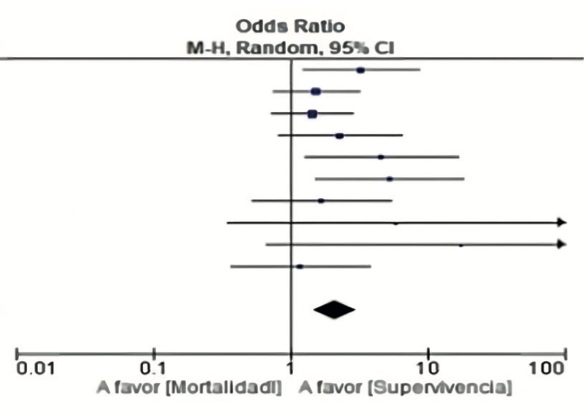

Yeisson Jhonas Rivero-Moreno, Samantha Redden-Chirinos, Marialejandra Paz-Castillo-López, Karen Bustamante-Zúñiga

|

|

|